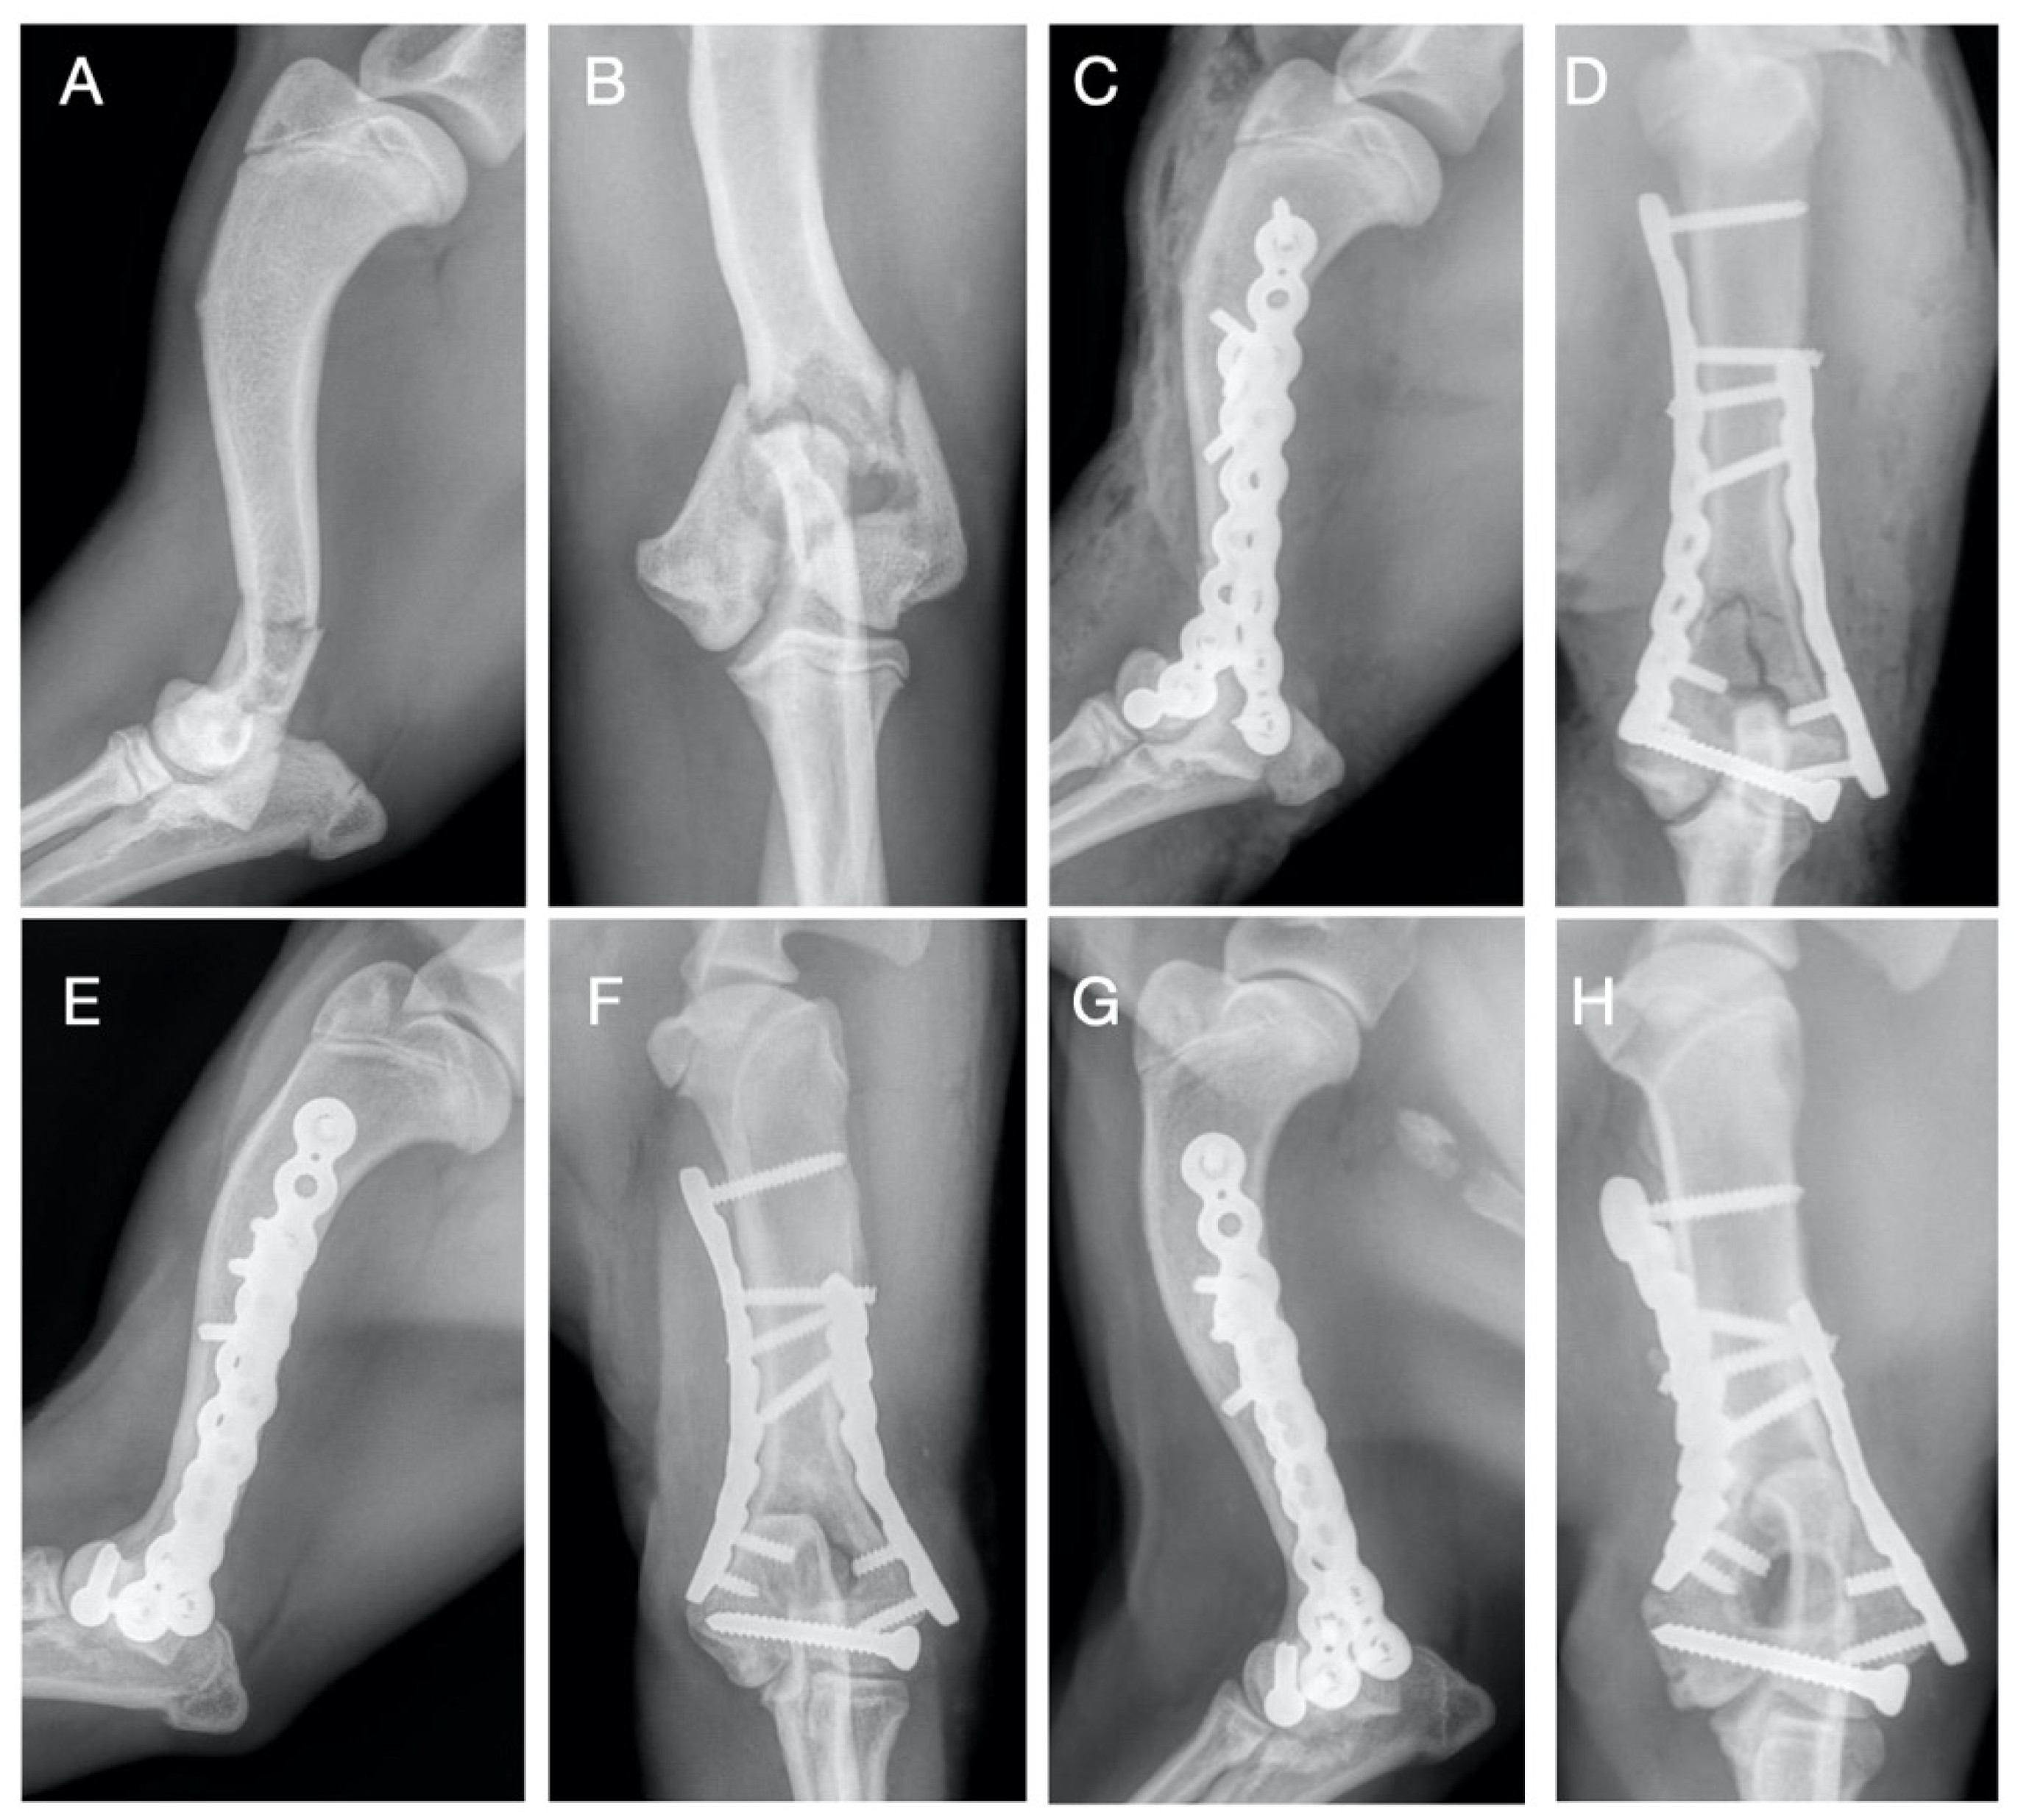

Figure 1.

Case 8. Preoperative (A,B) craniocaudal and medio-lateral projection showing simple distal humeral bicondylar fracture. Immediate postoperative (C,D) medio-lateral and caudocranial views showing a double 2,4 mm RP PAX plate and 2,7 mm transcondylar lag screw. Medio-lateral and caudocranial projections at 30 days (E,F) showing bone union at the diaphyseal fracture and primary reduction of the condylar fracture; follow-up 120-day radiographic evaluation (G,H) with medio-lateral and craniocaudal projections showing no implant failure.

All the fractures (14/14) were stabilized by the use of a double PAX plate (RP = locking reconstruction plates and/or SP = locking limited contact straight plates) and transcondylar cortical screw: medial SP 2.0 plate and lateral RP 2.0 plate in one dog weighing 4.2 kg (case 12); double RP 2.4 plate in one dog weighing 7.3 kg (case 8); double RP 2.7 plate in 4 dogs (cases 6-7-10-14) and medial SP 2.7 plate and lateral RP 2.7 plate in one dog (case 4) in patients between 9–14.5 kg; medial RP 3.5 plate and lateral RP 2.7 plate in 3 patients (cases 2-3-13) and medial SP 3.5 plate and lateral RP 2.7 plate in one dog (case 5) between 16.7–23 kg; double RP 3.5 plate in one dog weighing 25 kg (case 9); medial SP 3.5 plate and lateral RP 3.5 plate in two dogs (cases 1-11) between 28–38.5 kg. In seven dogs, 2.7 mm transcondylar cortical screws were applied; in six cases, 3.5 mm transcondylar cortical screws were used, and in one case, 4.5 mm transcondylar cortical screws were used. Additional supracondylar implants were applied in 7/14 cases, including cerclage wire (n = 1), position cortical screw (n = 4), lag cortical screw (n = 1) and Kirschner wires (n = 2) (Table 2). In the present series, a total of 118 screws were applied in 28 PAX plates; in particular, we used 61 screws proximal to the fracture with 36 screws positioned medially (range 2 to 4 and median value 2) and 25 screws were positioned laterally (range 1 to 2 and median value 2); 57 screws were inserted distal to the fracture with 29 screws positioned medially (range 2 to 3 and median value 2) and 28 screws positioned laterally (range 1 to 2 and median value 2). The median value of plate-screw density was found to be 0.57 calculated for both the lateral (range 0.40 to 0.80) and medial (range 0.44 to 0.87) sides. The post-operative radiographic study showed in each clinical case an adequate reduction of the fracture, without evidence of discontinuity of the articular surface and the alignment was adequate in all the cases performed. Although no intraoperative imaging supports (i.e., Fluoroscopy or intraoperative x-ray) were used, no locking screws were inserted in the joint space or within the fracture line. Bone healing assessed radiographically was obtained in all patients, except for case 13; the patient died fifteen days after surgery for causes not related to the surgical treatment. In 3/14 dogs, bone union was evident at the first post-operative FU at 30 days (Figure 1); in 8/14 dogs, the bone healing occurred between the first and the second postoperative FU; therefore, these fractures were considered healed at FU 60; in 2/14 patients, due to implant associated infection, bone healing was detected during the third FU at 90 days postoperatively. Radiographic study was performed at FU 120 to observe implant position and possible osteoarthritis development. In no case, implant failure, breakage or loosening of the screws occurred. OA was scored as follows: absent (6/14), mild (5/14) and moderate (2/14) and severe (0/14) (Table 1).